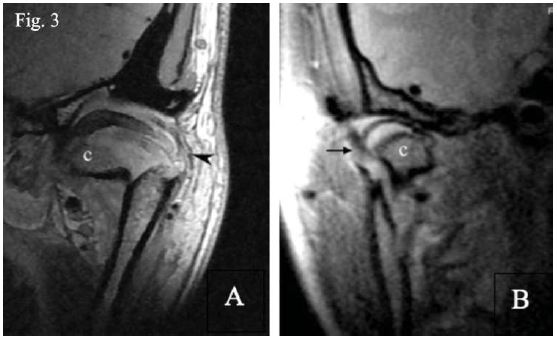

Con respecto a esta última estructura, resulta controversial si se observa o no en RNM. La mayoría de estudios no especifican8,25,32, pocos afirman que no24, otros sólo frente a casos de patologías o distención por efusión23,28,29,33, siendo muy pocos los que afirman que sí puede verse15,17 (figura 3), otros a raíz de casos de fractura como Kim et al.34, sólo mencionan que se observa como una línea oblicua (figura 4), pero pero no especifican dónde se encuentra; Sun y Wan mencionan su ruptura y presentación como una masa expansible al canal auditivo18. Sin embargo, ninguno especifica cómo es que se ve. Sakhavalkar et al.35, en el año 2016 publicaron un estudio evaluando y midiendo el ancho de la cápsula articular, basados en parámetros indirectos, pero tampoco especifican cómo se observa.